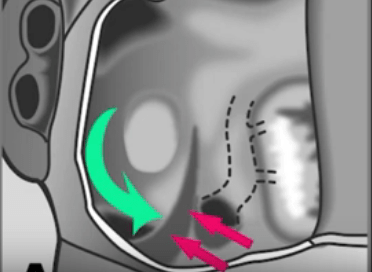

CS Atresia+Unroofed CS with patent vein of Marshall case example.

CS Atresia+Unroofed CS Vein of Marshall Occluded